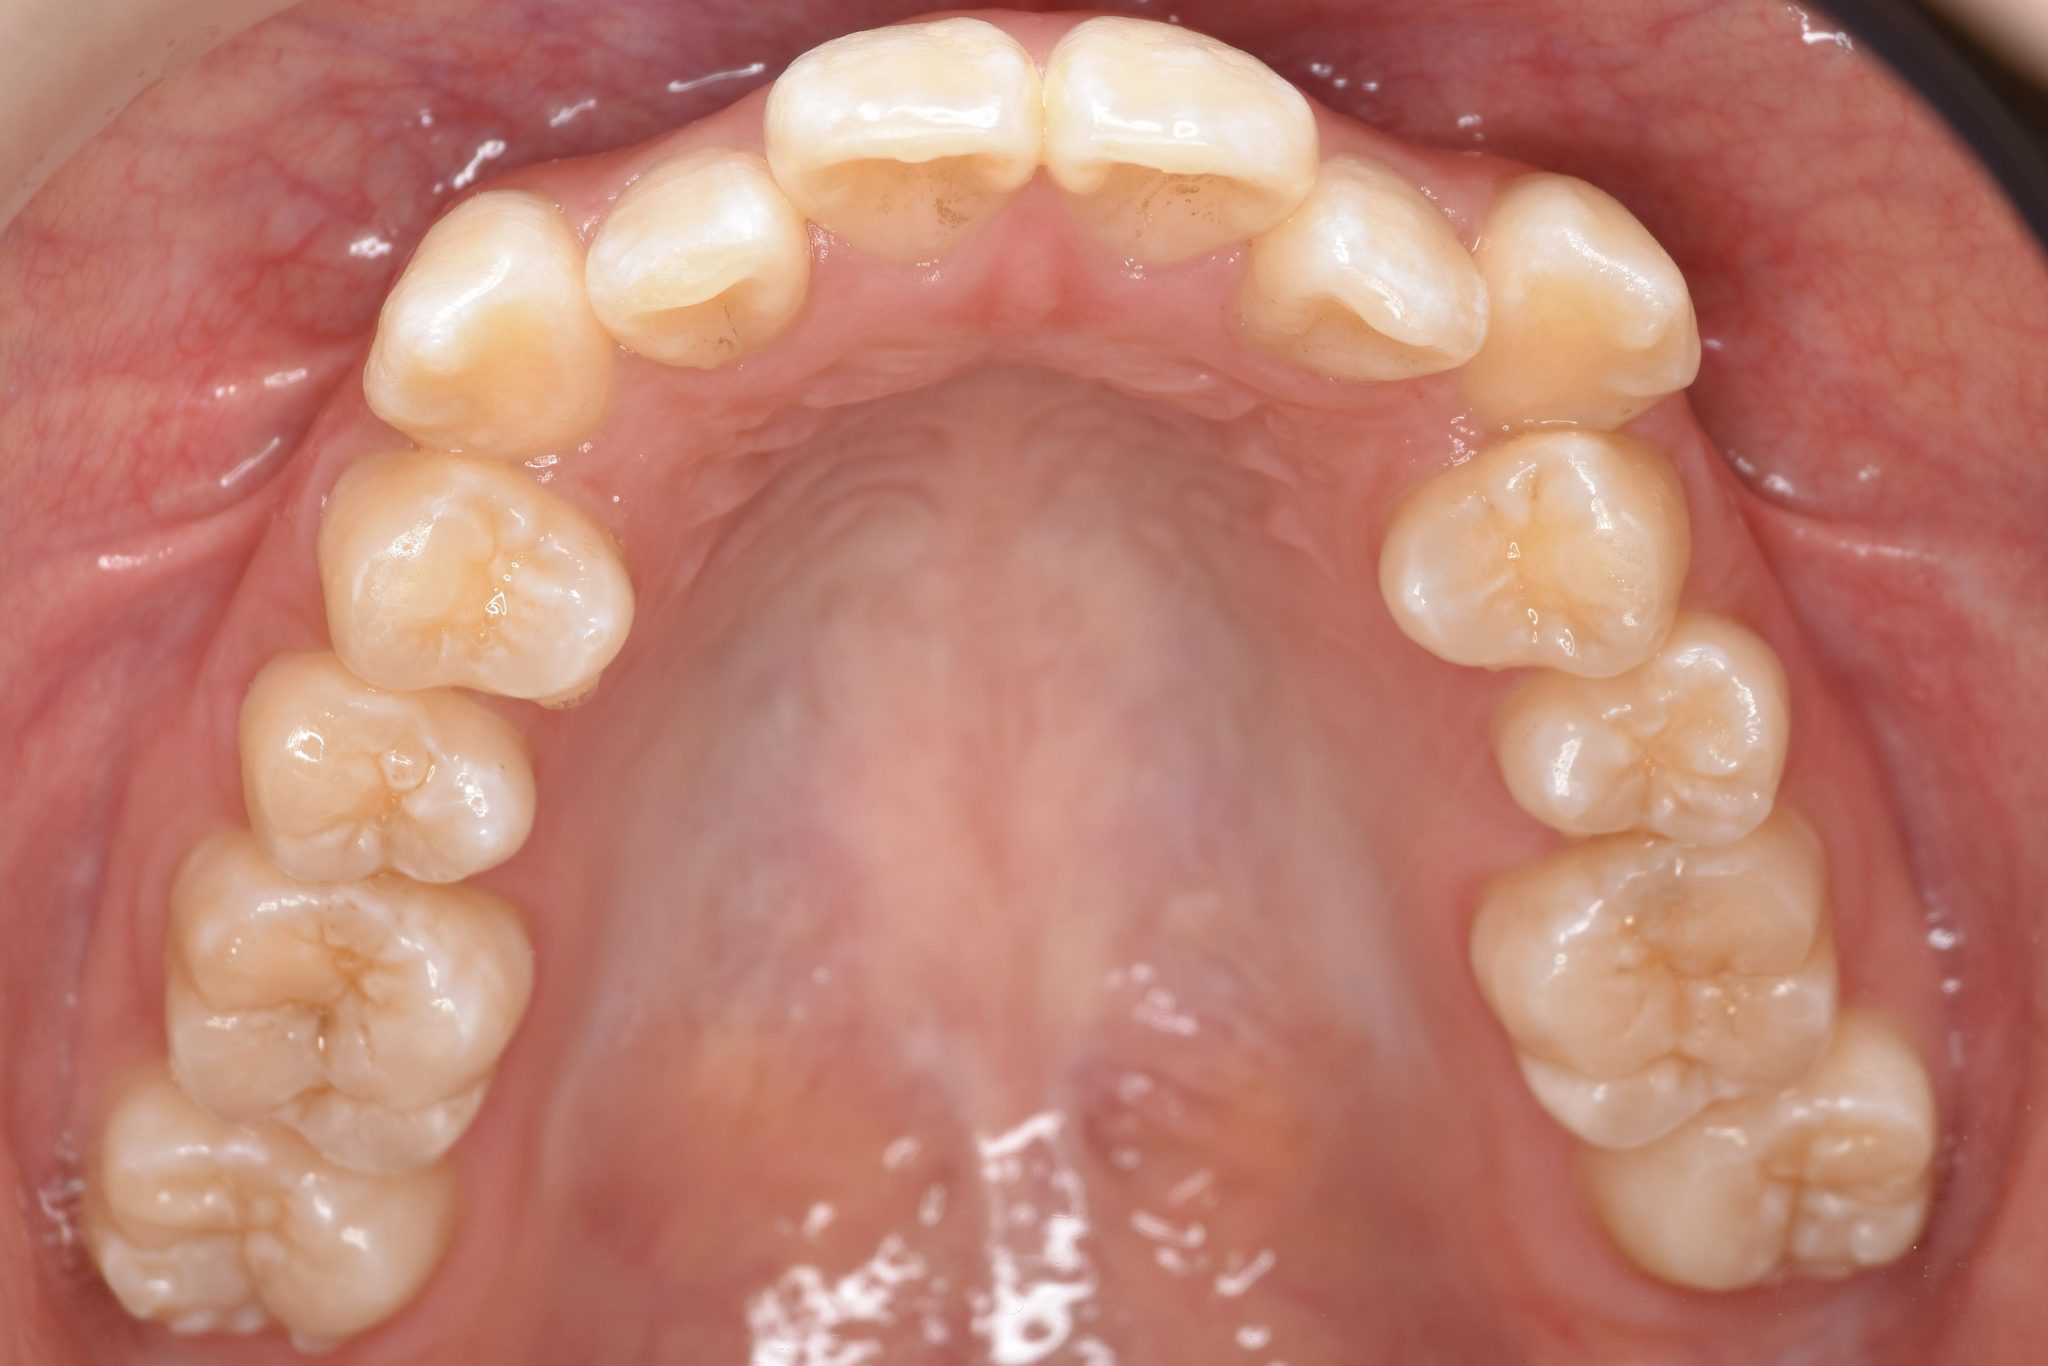

ビフォー

全顎ワイヤー矯正 症例_815

アフター

主訴 前歯の出っ歯|八重歯|下の歯のデコボコ|検診で噛み合わせが悪いと指摘されたこと

施術内容 成人矯正1期治療

治癒期間 1年4か月間

費用 954,800円(税込)